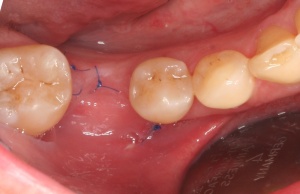

Die Entscheidung für eine regenerative oder eine resektive Therapie (Modul D des Berner Modells) richtet sich nach der knöchernen Defektkonfiguration. Schwarz und Becker (2007) unterschieden in: I. eine horizontale Knochenresorption, II. eine schüsselförmige Knochenresorption, III. eine trichterförmige Knochenresorption und IV. eine spaltförmige Knochenresorption. Wie in der Parodontalchirurgie sollte – soweit vorhanden – mikrochirurgischem Instrumentarium der Vorzug gegeben werden. Die engen periimplantären Verhältnisse bei aufgesetzter Implantatprothetik machen dies notwendig. Der primäre Wundverschluss sollte mit Nahtmaterial 5-0 bis 7-0 erfolgen (Abb. 12, 13, 14, 15, 16).

Dies lässt sich exemplarisch auch im folgenden Fall zeigen: Ein männlicher Patient mit der Diagnose einer generalisierten aggressiven Parodontitis (32 Jahre) befand sich zunächst in einer systematischen antiinfektiösen nichtchirurgischen Parodontitistherapie mit begleitender systemischer Antibiose. An der nachfolgenden unterstützenden Parodontitistherapie nahm er jahrelang teil (2007 – heute) und wies eine sehr gute Compliance auf. Im Oktober 2012 erfolgte durch mich die Implantation regio 34. Ein Jahr post implantationem zeigen sich unverändert kein periimplantärer Knochenabbau sowie klinisch gesunde Gingivaverhältnisse und physiologische Sondiertiefen (Abb. 18).